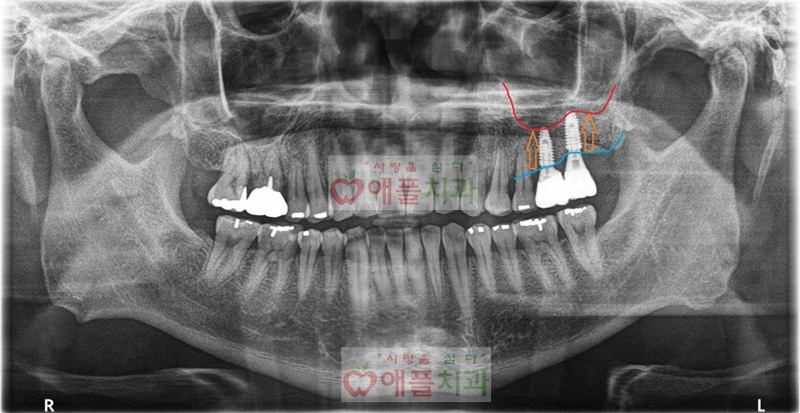

<상악동 거상술 + 임플란트 치료 후>

예전에 좌측 상악 임플란트 식립을 위해서는 상악동 골이식(=상악동 거상술)이 필요하다는 설명을 들으셨고, 상악동 골이식이 어렵고 난이도가 높은 수술인 만큼 저희병원을 찾아주시고 믿고 시술을 진행하셨습니다.

치료 진행하면서 별다른 합병증이나 특이 사항은 없었으며, 현재 잘 사용하고 계십니다.

3-4개월 주기마다 애플치과에 방문하셔서 정기적인 케어 받으시면 자연치아 처럼 오래 사용하실수 있을것 같습니다.